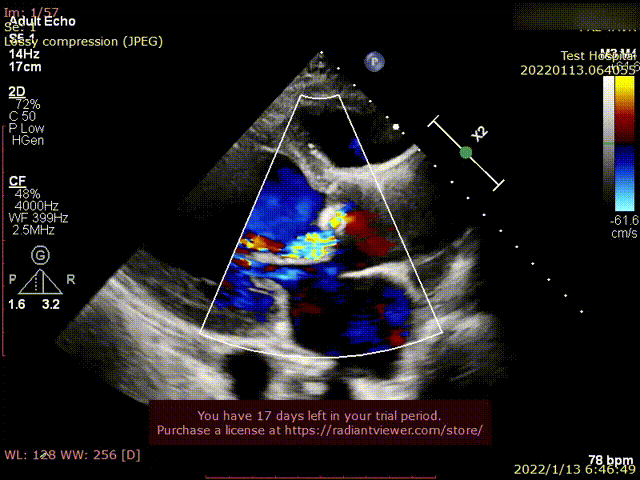

术前超声影像

术后超声1

术后超声2